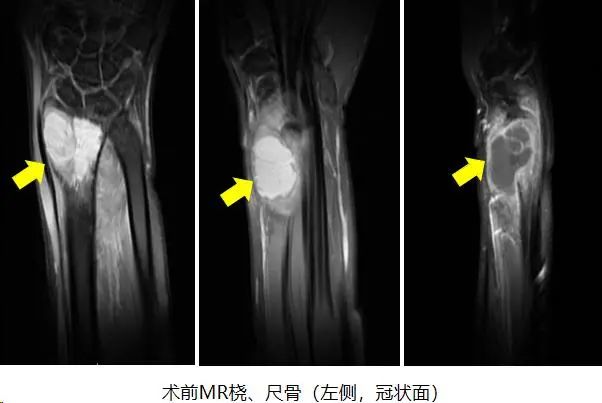

结合影像学检查结果以及病理穿刺结果,可以明确诊断为左侧桡骨骨巨细胞瘤 III级,首选手术切除病灶;且具有侵袭性的III级,则需要彻底完整切除肿瘤以及行桡骨重建手术。

经过精确测量发现,手术需要切除患者包括桡骨远端关节面在内的瘤段至少7cm,手术切除瘤体后桡骨局部缺损巨大,可以利用先进的3D打印技术,打印一个定制假体,匹配度高,手术时间较短且方便简单。